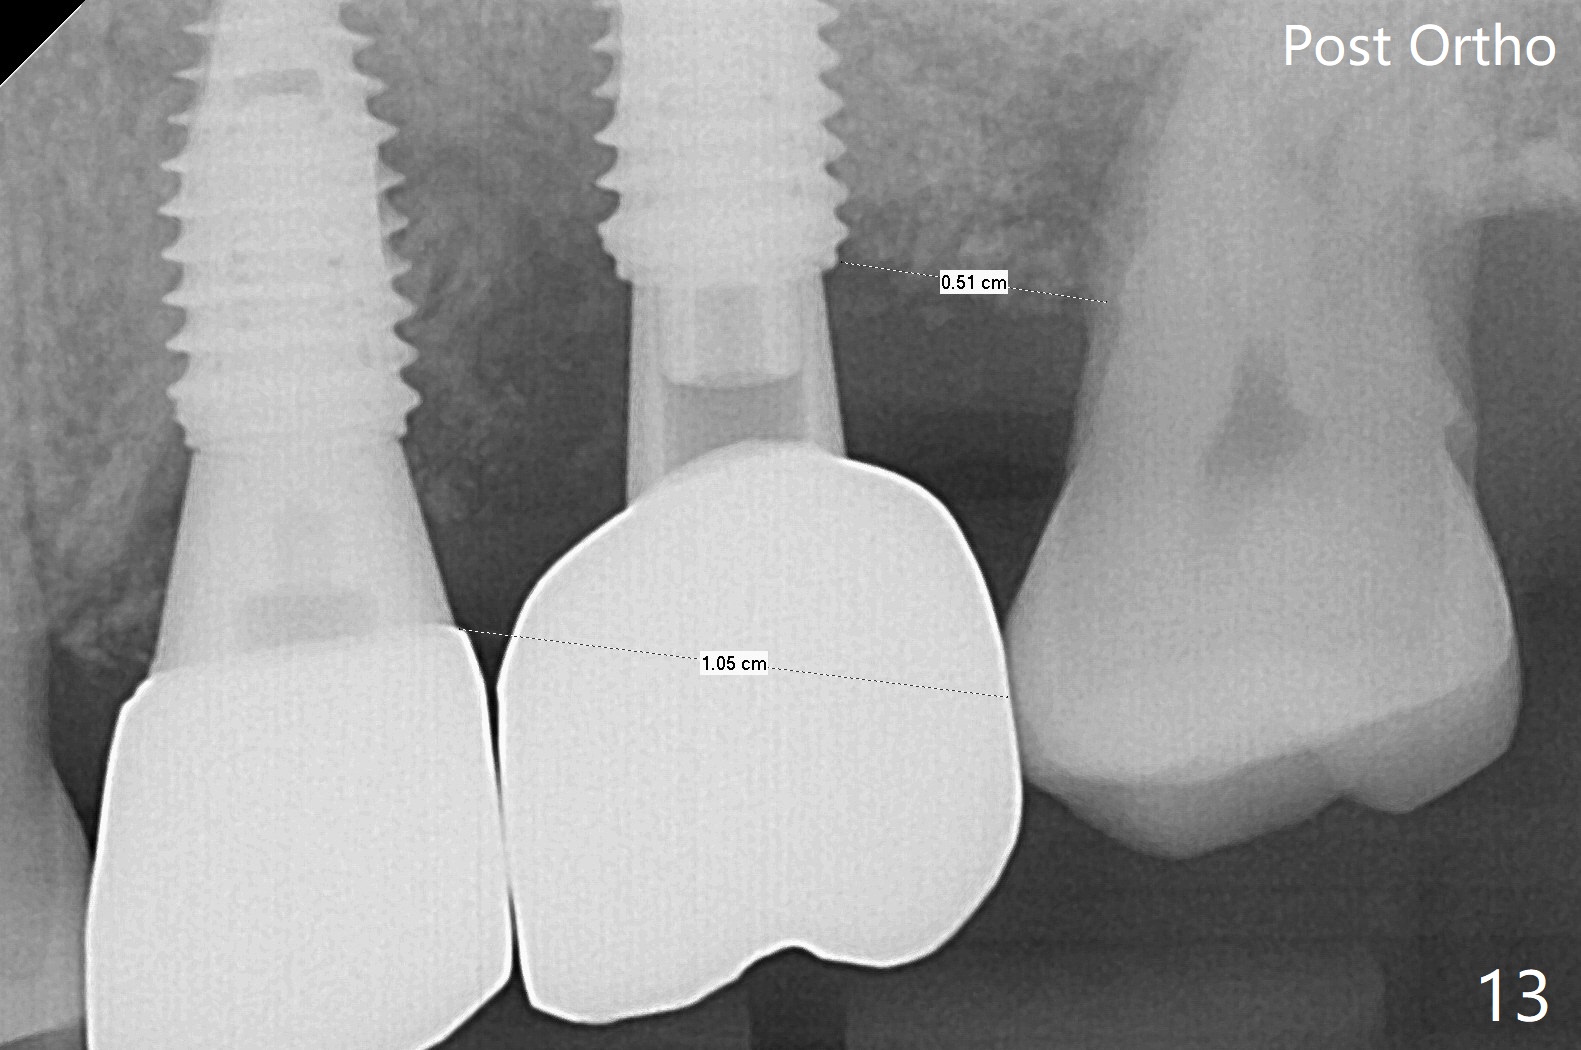

左上六植牙第三次失败后五个月,牙槽嵴宽度尚可,切开后放置导板,3.2乘19毫米园钻头好像接近上颌窦底板(图一),但是粘性骨块和4乘10毫米报废植体就不能进入上颌窦(图二),最后不得不使用3毫米Bicon骨凿,之后同一个报废植体就似乎进入上颌窦(图三),4.5乘8.5毫米正式植体植入深度和稳定性均正常(图四),腭侧植体稍微暴露,放置愈合螺丝后,放置骨粉和PRF膜,缝合,左上5植体放置5.7x4.5(4)毫米基台,固定牙周敷料。术后5.5个月植体好像整合(图五),缺牙间隙特别小,5临时牙冠(P)必须取出才能切开暴露植体,放置5.5x5毫米愈合基台(图六)。伤口愈合后,必须做渐进性负荷,之后做简单局部矫正,推7往远中,6缺失3年,7往近中倾斜移位。两周后牙周敷料脱落,伤口愈合,放置修复基台,故意将基台平面朝远中,足够空间制作临时牙冠(图七)。调整基台长度(比较图七,八)。制作连体牙冠(5,6),有意提高5牙冠高度,使左上7不与对合牙接触,有利于远中移位(图九)。也要在对侧提高咬合(图十)。局部矫正一个月后,磨去右侧咬合垫和磨短左上5,6临时牙冠,前牙还不能完全接触(图十一)。1-2星期前牙开合自行消失,取模做左上5,6牙冠。局部矫正似乎使左上7远中移位大约3毫米(比较图十二,十三)。粘固拧紧后(20 Ncm)14号牙牙冠咬合增高,拍摄根尖片(图十三),两个基台好像仍然完全就位,然后调整咬合。